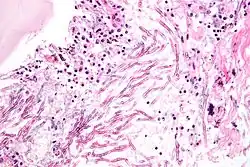

Infecting C. neoformans cells are usually phagocytosed by alveolar macrophages in the lung.[11] The invading C. neoformans cells may be killed by the release of oxidative and nitrosative molecules by these macrophages.[12] However some C. neoformans cells may survive within the macrophages.[11] The ability of the pathogen to survive within the macrophages probably determines latency of the disease, dissemination and resistance to antifungal agents. In order to survive in the hostile intracellular environment of the macrophage, one of the responses of C. neoformans is to upregulate genes employed in responses to oxidative stress.[11]